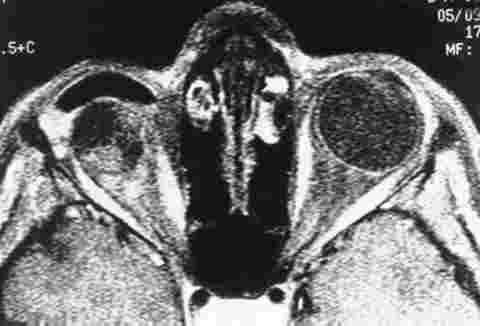

Figura 2

RNM, IMÁGENES EN T1 CON SUPRESIÓN GRASA TRAS ADMINISTRACIÓN DE Gd-DPTA. CAPTACIÓN DISCRETA DE CONTRASTE, LIMITADA FUNDAMENTALMENTE A LA PERIFERIA.